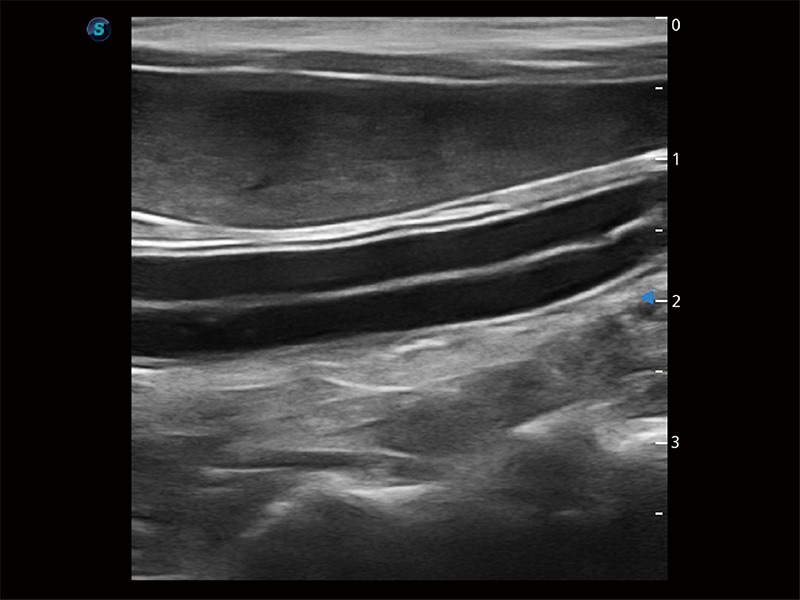

优异的基础图像

ProPet 80 全新的动物超声智能软件和丰富的探头群,为动物医生提供了高清晰度和精细分辨率的图像,无论在宠物、马科、畜牧还是实验室动物等应用中都可以轻松应对,为您的日常工作带来满意的体验。

(犬)肝脏

(猫)胆囊

(犬)胎儿主动脉弓立体血流

(犬)四腔心MQA

(犬)肠道

(犬)肾脏显微血流

(犬)胎儿四腔心

(猫)二尖瓣M型

(犬)二腔心血流